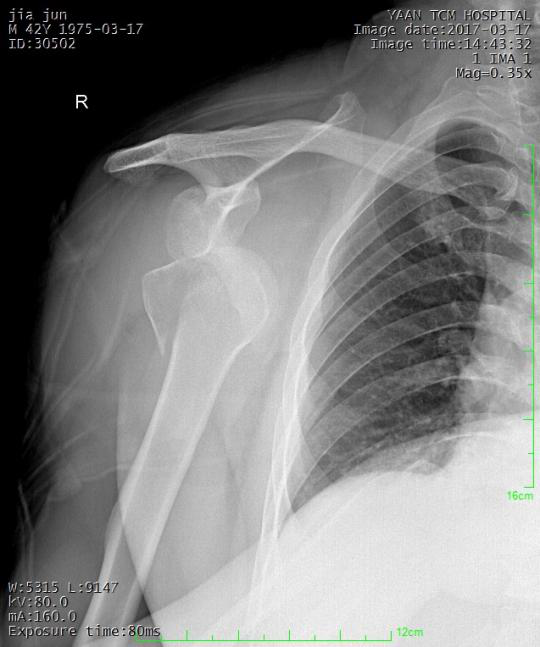

医院目前设立一院二区,院本部和医养中心院区,占地20余亩,总规模3.3万平米。拥有血管造影X射线系统(DSA,荷兰PhilipsMedical)、电生理记录系统、血管内超声波诊断仪(美国波士顿)、GE128排螺旋CT、奥泰1.5T超导磁共振、四维彩超等先进的大中型医疗设备和全层流净化手术室及ICU。开设了39个临床医技科室,编制床位500张,医院现有职工761人(含劳务派遣),其中:高级职称101人,中级职称187人,博士生1人,研究生52人。拥有四川省名中医3名、首届岐黄菁英人才2名、省中医药管理局学术技术带头人后备人选2人,市卫生健康委学术技术带头人5名,市卫生健康委学术技术带头人后备人选6名,市、区级名中医8人。

医院坚持中西医并重,不断提升综合实力。关节外科、脊柱外科、血管外科、修复重建显微外科等优势学科在全市处于领先地位,服务半径从雅安辐射至川西。普外科、泌尿外科、神经外科、胸外科、呼吸内科、消化内科、心血管内科、肾病内科、妇产科、儿科等蓬勃发展;急诊急救和重症医学科、医技检查等科室蒸蒸日上。

医院注重医、教、研发展,拥有十二五”国家中医重点专科协作组成员单位1个(骨伤科);省级重点专科4个:骨伤科、康复科、脾胃病科、肾病科;在建省级中医重点专科2个:老年病科;分泌病科;市级重点专科15个:颈肩腰腿痛科、周围血管外科、泌尿外科、重症医学科、麻醉科、治未病科、心血管内科、中医护理专科、超声医学科、临床中药学、急诊科、中医妇产科、放射科、肺病科、针灸科。